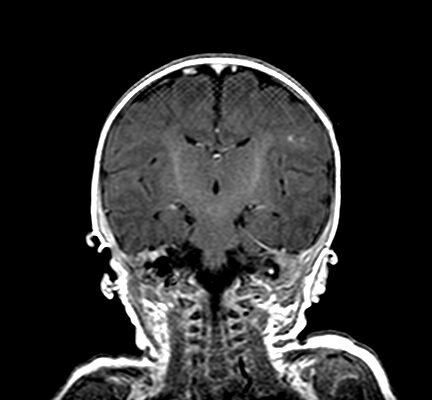

Clinical and Radiologic Features of Fulminant Pediatric Autoimmune Encephalitis: A Case Report

DOI: https://doi.org/10.21980/J8JW75The neurology service was consulted in the ED and multisequence MRI and MR angiography (MRA) of the brain were obtained without and with IV contrast. Diffusion-weighted imaging (DWI) and T2-weighted-Fluid-Attentuated Inversion Recovery (FLAIR) sequences showed multifocal small areas of diffusion signal abnormality in the brainstem and basal ganglia (red asterisks) suggestive of ischemia. Additional multifocal bilateral supra- and infratentorial foci of signal abnormality including subcortical white matter and deep grey matter were highly concerning for encephalitis or demyelinating disease. MRI was repeated on day 3 and day 7 during evolution of disease.